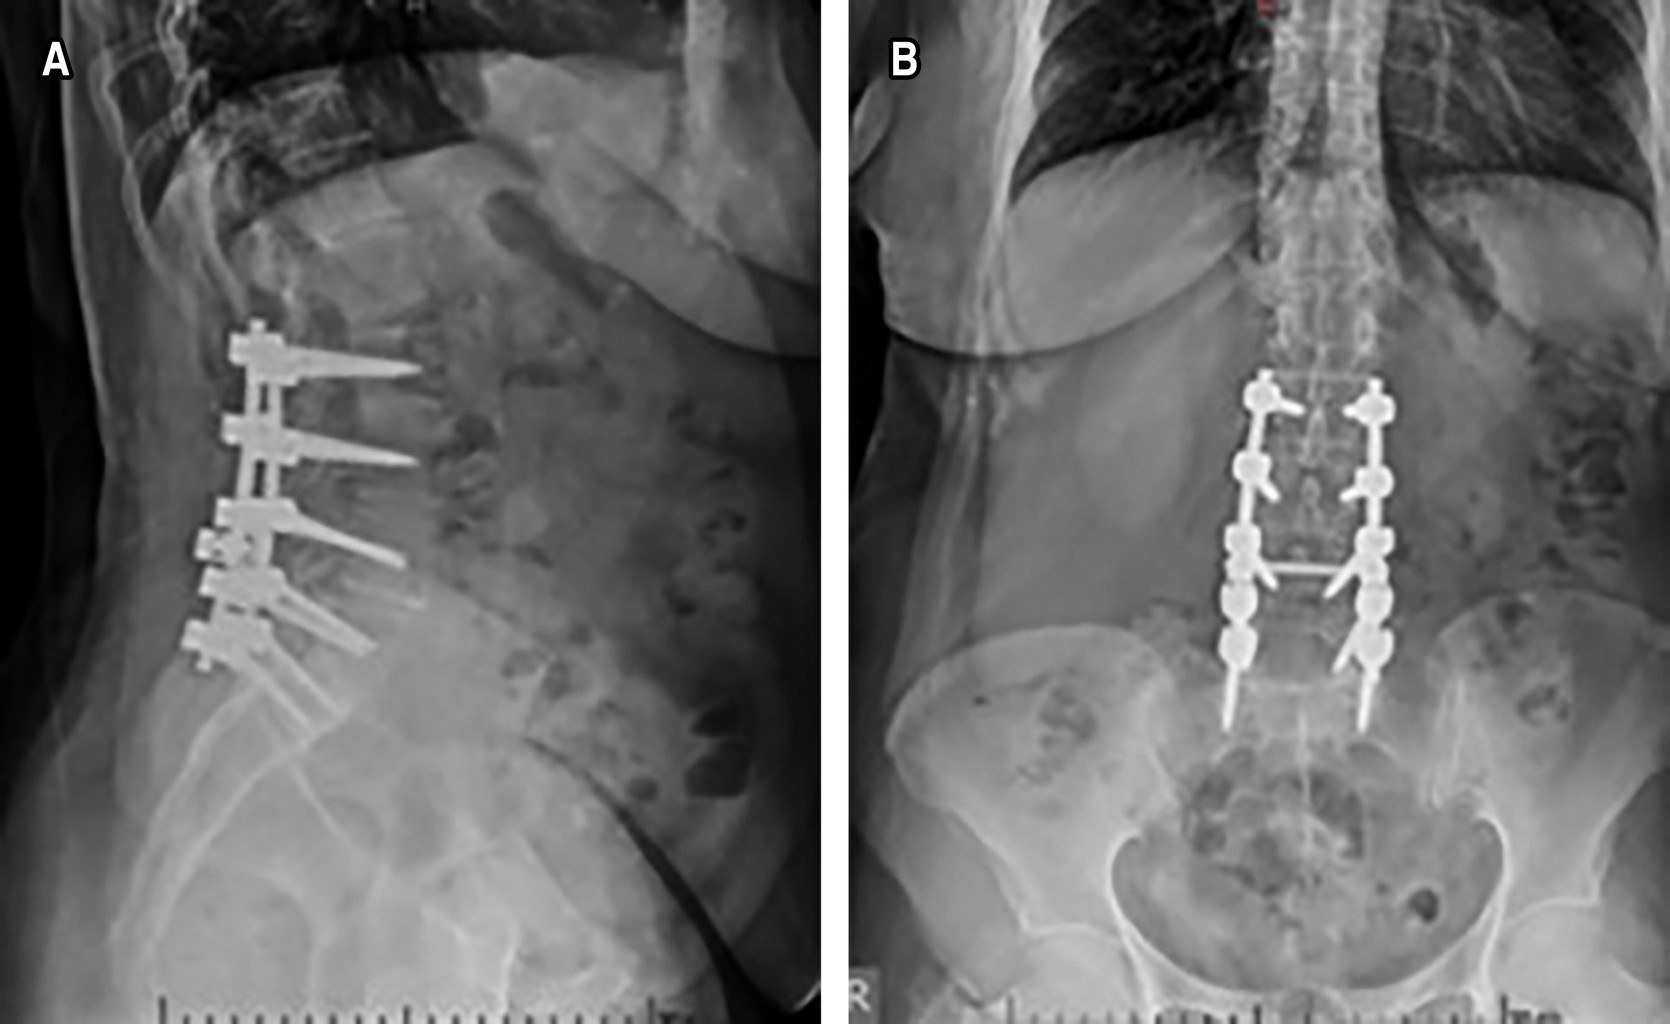

Se recabó información de un total de 40 pacientes con diagnóstico de CLE degenerativo, que fueron sometidos a recalibraje, ligamentoplastía y artrodesis posterolateral con instrumentación con tornillos y barras (Figuras 1 y 2). Los niveles instrumentados más frecuentes fueron L3-L5 en 35% y L5-S1 en 10%. La distribución por sexo fue 57.5% (n = 23) mujeres y 42.5% (n = 17) hombres. El rango de edad fue de 45-76 años, con promedio de 65 años. Las tres ocupaciones más frecuentes fueron: docente (25%), ama de casa (17.5%), policía (10%). En cuanto a los síntomas previos a la cirugía existieron 32 (80%) pacientes que referían una intensidad del dolor lumbar de 7/10 y ocho (20%) casos con 8/10 en la escala numérica del dolor. Referente a la fuerza de las extremidades pélvicas hubo 26 pacientes (65%) con 4/5 en la escala de Daniels, y seis casos (15%) que referían parestesias en ambas piernas. En los datos obtenidos seis meses posteriores a la cirugía, se observó que 85% de los pacientes refirieron un dolor de intensidad 3/10 y 15% intensidad 4/10. Los 26 pacientes con fuerza 4/5 mejoraron a 5/5 en la escala de Daniels. Cinco de los seis pacientes que tenían parestesias, mencionaron que estas desaparecieron (Tabla 1). El índice de discapacidad de Oswestry previo al evento quirúrgico fue de 42% en promedio, de 25% a los seis meses y de 18% a los 12 meses posterior a la cirugía.

La lumbalgia secundaria a CLE es un padecimiento común, que puede pasar por alto al menospreciar la sintomatología y, por ende, no realizar un adecuado estudio del caso mediante la anamnesis y realización de estudios auxiliares de diagnóstico. Conociendo la alta incidencia y prevalencia de este padecimiento, debe realizarse un enfoque en el protocolo de tratamiento con la finalidad de obtener el mejor resultado y pronóstico en el paciente. En nuestra serie, los resultados muestran que la edad avanzada está presente en la mayoría de los pacientes con CLE degenerativo, lo cual coincide con la literatura internacional; sin embargo, no es exclusiva de la tercera edad; y que el género femenino es el más afectado. En este trabajo se realizaron técnicas quirúrgicas descompresivas como laminectomía y foraminectomía, con instrumentación con tornillos transpediculares con mayor frecuencia en los niveles L3-L4 y L4-L5, lo que se apega a los reportado en otros países.21 Con los resultados obtenidos en el índice de Oswestry en los pacientes, se puede considerar que la técnica y el manejo fueron efectivos, al presentar una disminución de la discapacidad funcional a los seis y 12 meses postoperatorios en comparación a la valoración prequirúrgica, siendo el recalibraje, la ligamentoplastía y la artrodesis posterolateral con instrumentación con tornillos y barras, un tratamiento que proporciona al paciente una evolución funcional favorable por CLE degenerativo. Recomendamos la inclusión de esta técnica quirúrgica en el tratamiento de pacientes con CLE degenerativo en los cuales el manejo conservador ha fallado, así como su enseñanza a residentes de traumatología y ortopedia. Además, consideramos que este trabajo puede servir como base para estudios posteriores de manera prospectiva, controlada y aleatorizada.